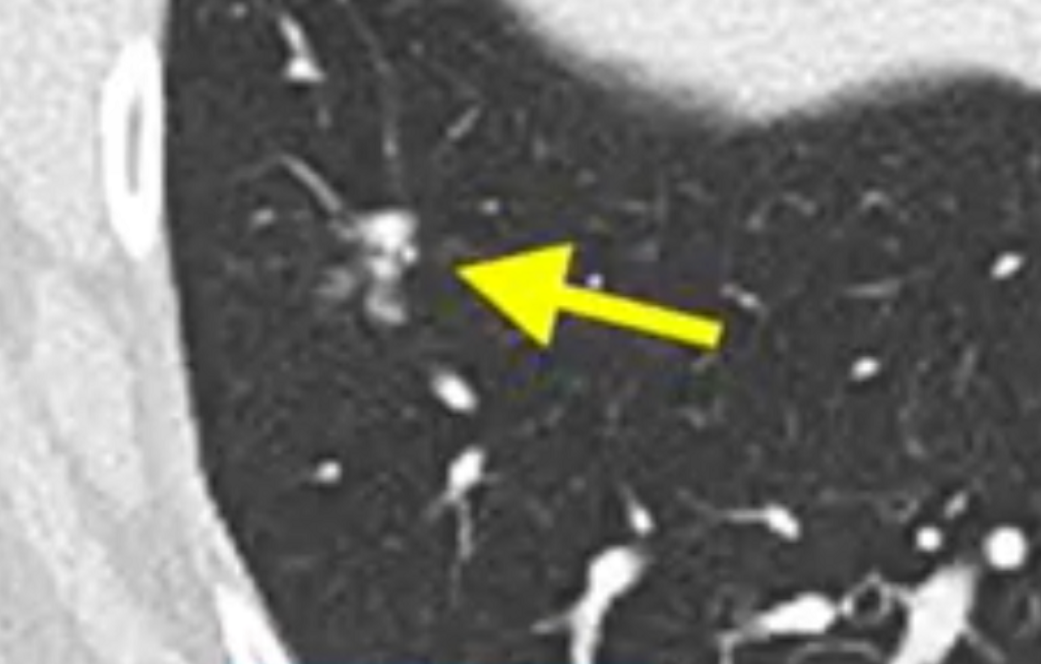

癌症免疫疗法的出现 , 已经给越来越多的晚期患者带来了重生的希望 。 近期国外研发的一款全新的免疫疗法 , 先后登上了国际重磅的《Nature》 , 《Science》 , 《新英格兰医学》等期刊 , 让多名经历了无数治疗失败后的患者得到了完全缓解 , 这是真的吗?我们先来看看已发表的研究案例 。

《Science》:迈向第二个十年!晚期胆管癌患者找到新疗法晚期胆管癌Melinda Bachini患者在生命垂危之际参加了美国国家癌症研究院Dr. Steven Rosenberg团队研发的最新的免疫疗法的临床试验 , 这个团队是世界最顶尖的免疫疗法小组之一 , 使用高度个性化的方案攻击并治愈Melinda Bachini的肿瘤 , 这个重大的突破在2014年被发表在国际顶级的期刊《科学》上 , 她的抗癌经历也给无数患者带来了信心 。

故事开始于2009年 , Melinda Bachini被确诊为晚期胆管癌 , 这种癌症在当时属于罕见癌症 , 在美国 , 每年确诊的人数还不到8000人 , 医生说 , 他们对于这类癌症治疗的经验有限 , 只治疗过少数患者 , 但是可以确定的是 , 没有一个患者能活过两年 。

他们咨询了著名的梅奥诊所 , 对于Melinda的病情 , 手术是当时唯一的选择 。 然而肿瘤并没有轻易的放过她 , 复发 , 化疗 , 再复发 , 再化疗 。。。 直到最强的治疗方案让Melinda的头发掉光了 , 浑身疼痛 , 甚至已经丧失了活着的尊严和意义 , 这一切也无法阻止肿瘤在体内蔓延 , Melinda决定放弃化疗 。 即便不敢想象孩子们没有妈妈的生活 , 但前提是必须有质量地活下去 。